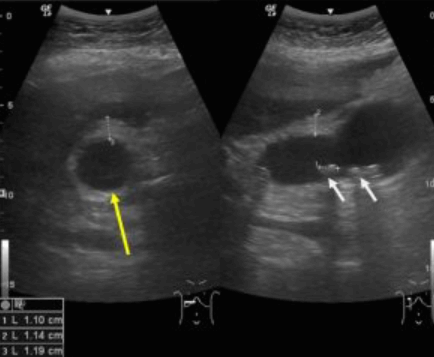

US finding

- 반복된 염증에 의한 담낭벽 비후 (5mm 이상)

- 담낭 내 담석

- 시간이 지남에 따라 담낭은 위축된다 (retracted GB)

- 벽침윤형 담낭암과 감별이 어렵다